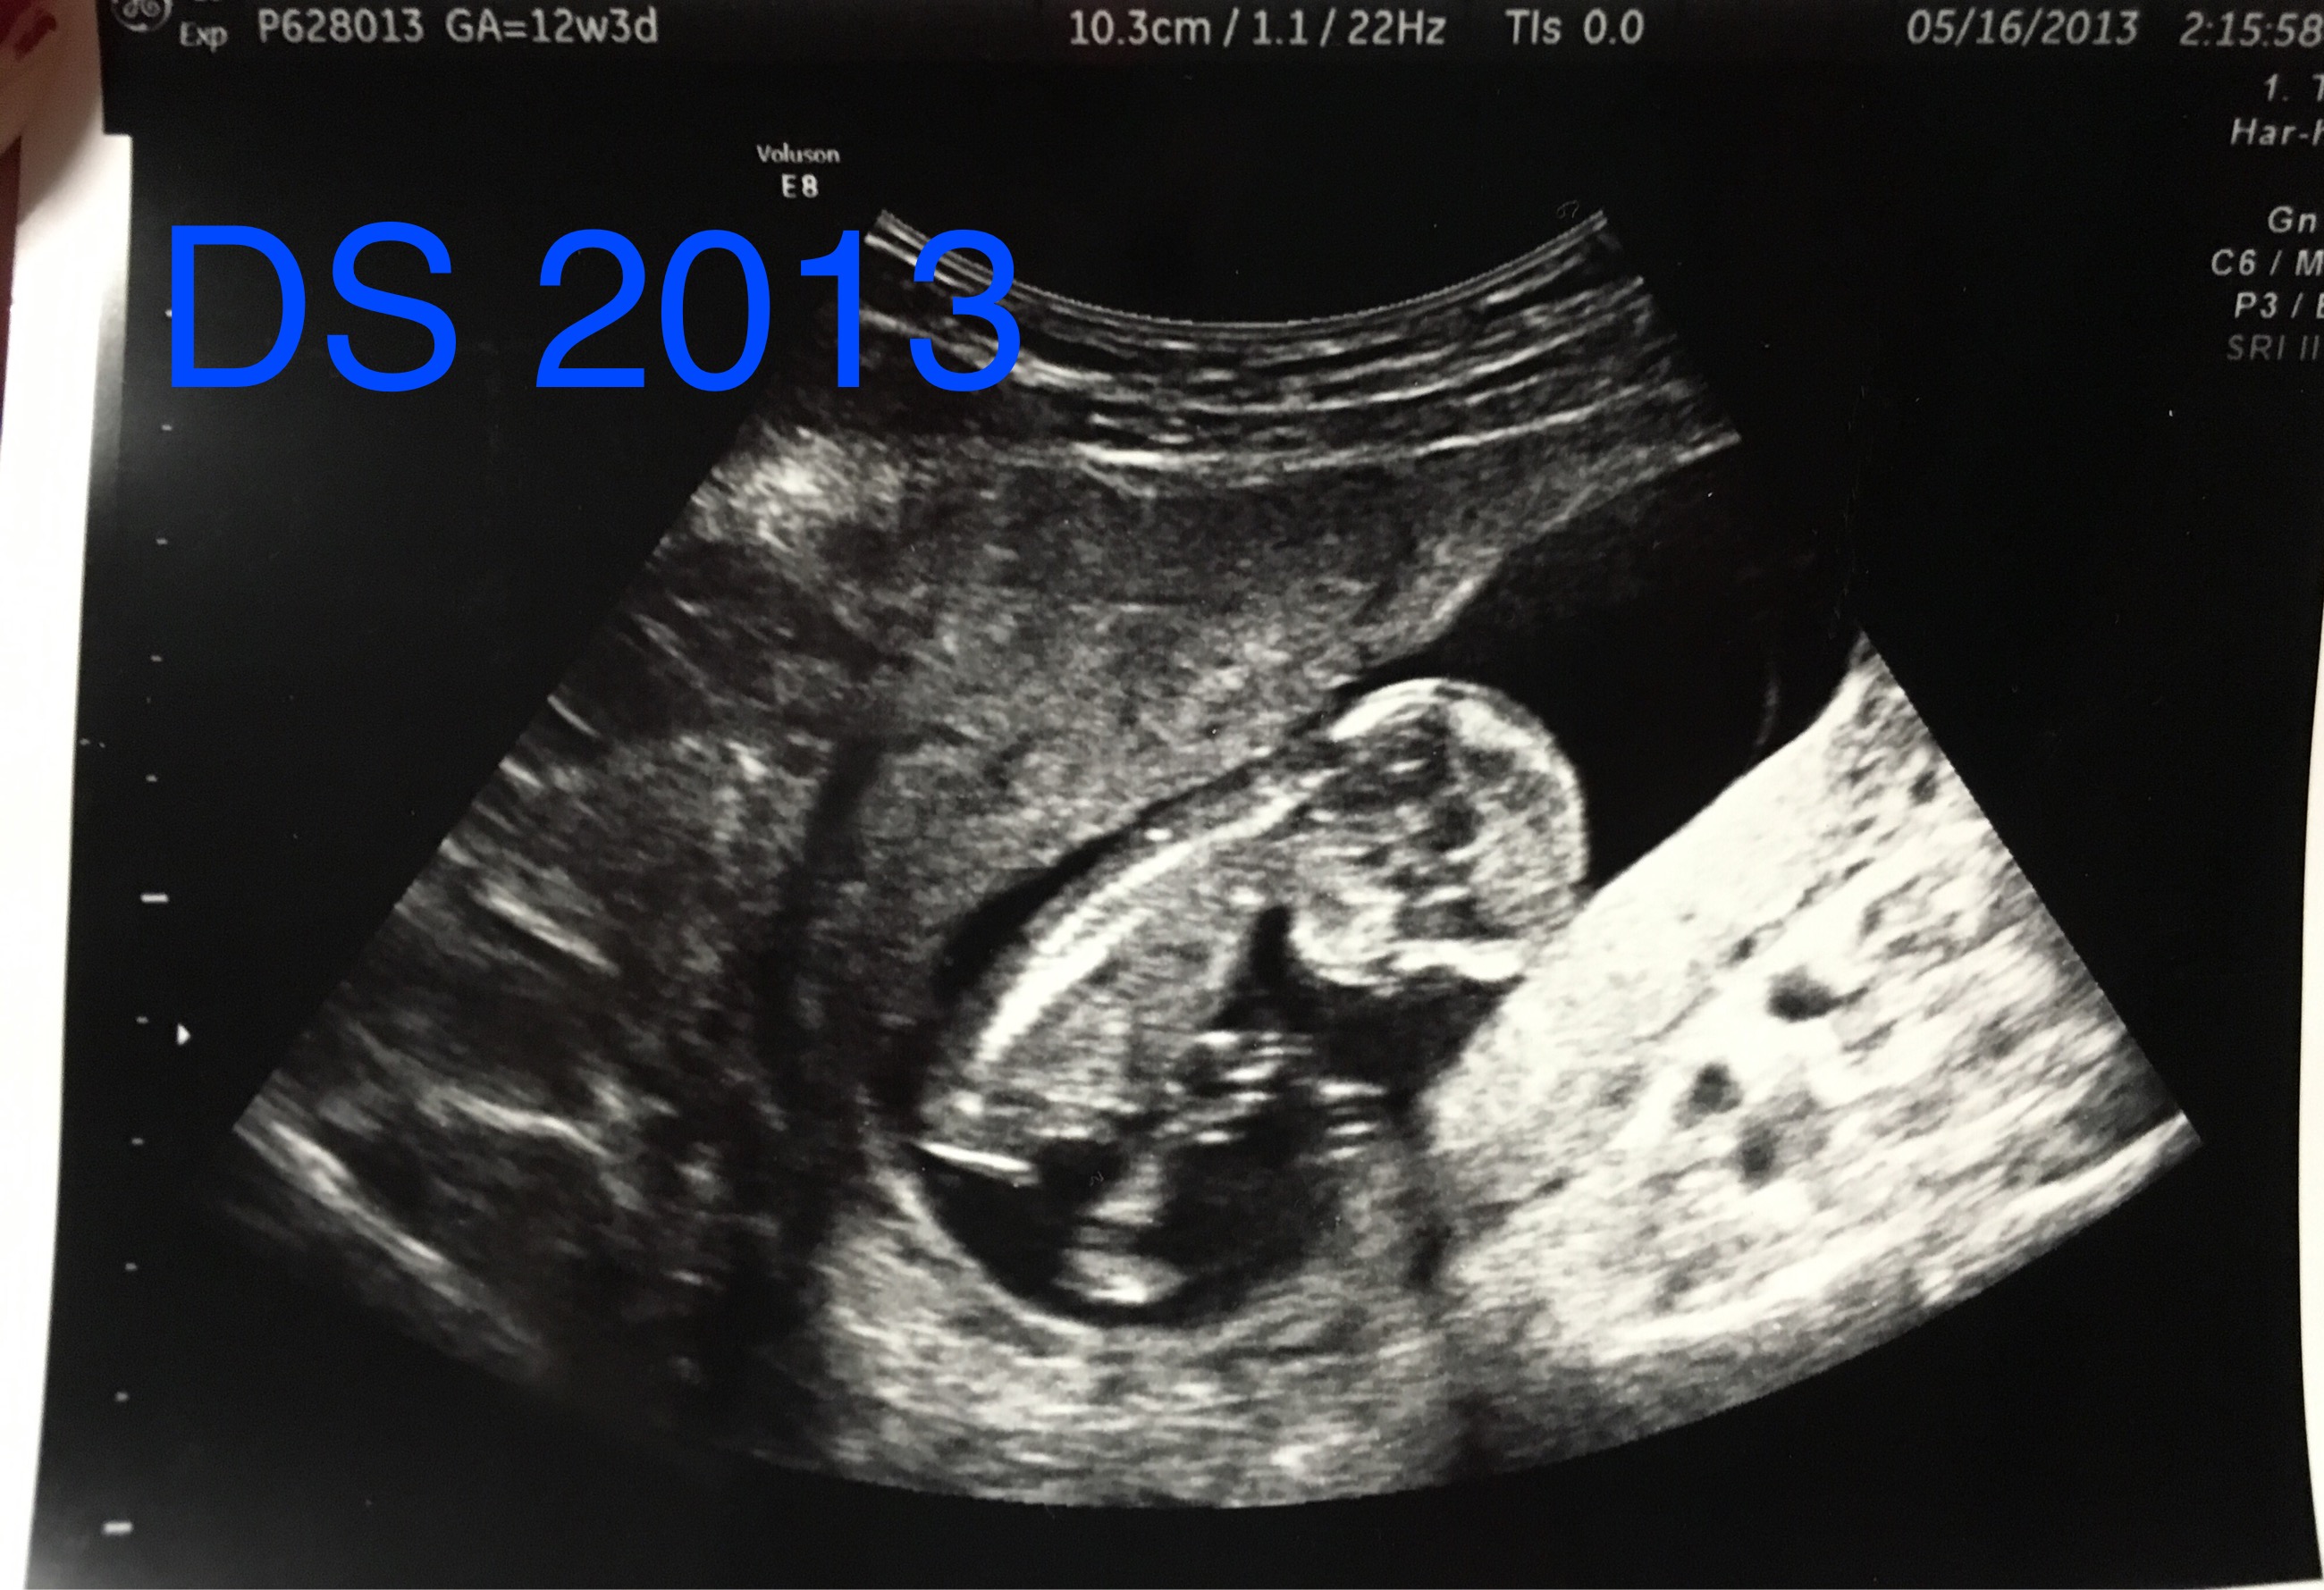

Below are my 12+4 week scan shots, I'm hoping for some gender guesses. Is the nub even visible? I've looked at tons of pics online and can't seem to make out the nub in my pic. I'm kind of thinking boy, this bub looks so much like my DS around the same time (in regards to skull shape, although this baby has a flatter face). I've attached pics of DS as well.

And here is DS 1:

Attachment 29172